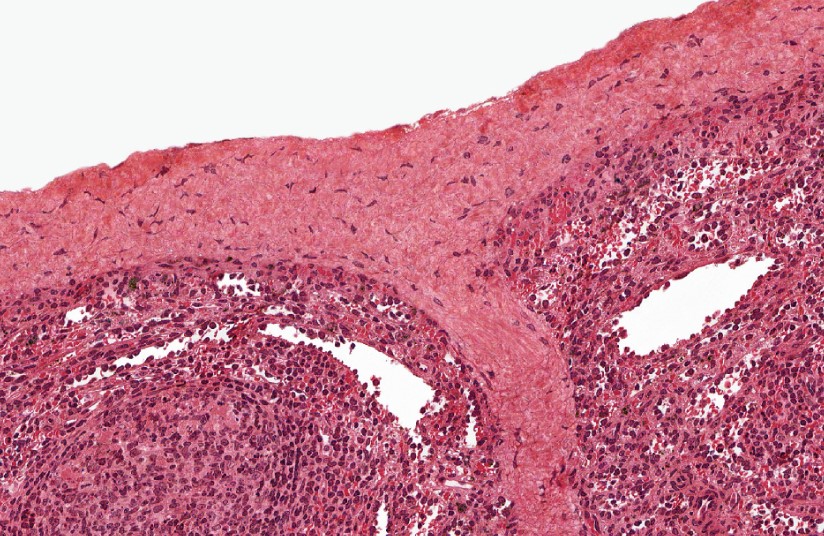

AMÍGDALAS

Faríngeas: revestidas de epitelio respiratorio. Palatinas: revestidas de epitelio plano estratificado.

Observe el epitelio respiratorio que reviste las tonsilas faríngeas.Las amígdalas son acúmulos diferenciados de folículos linfoides situados debajo del epitelio de revestimiento de los puntos de entrada al tubo digestivo y al aparato respiratorio.Identifique el epitelio de revestimiento y las criptas palatinas.Las criptas palatinas son espacios en forma de «grietas» y son características de las amígdalas.El epitelio plano estratificado sin estrato córneo reviste las tonsilas palatinas,Amígdala palatina, HyE. Observe los nódulos linfoides secundarios.Recuerda que la amigdalitis es especialmente común en los niños y a menudo acompaña a una faringitis. Amígdala palatina, HyE.Las amígdalas son estructuras parcialmente encapsuladas que carecen de vasos linfáticos aferentes pero que están drenadas por vasos linfáticos eferentes. Amígdala palatina, HyE.Observe la enorme cantidad de nódulos linfáticos que tienen las amígdalas. Amígdala palatina, HyE.